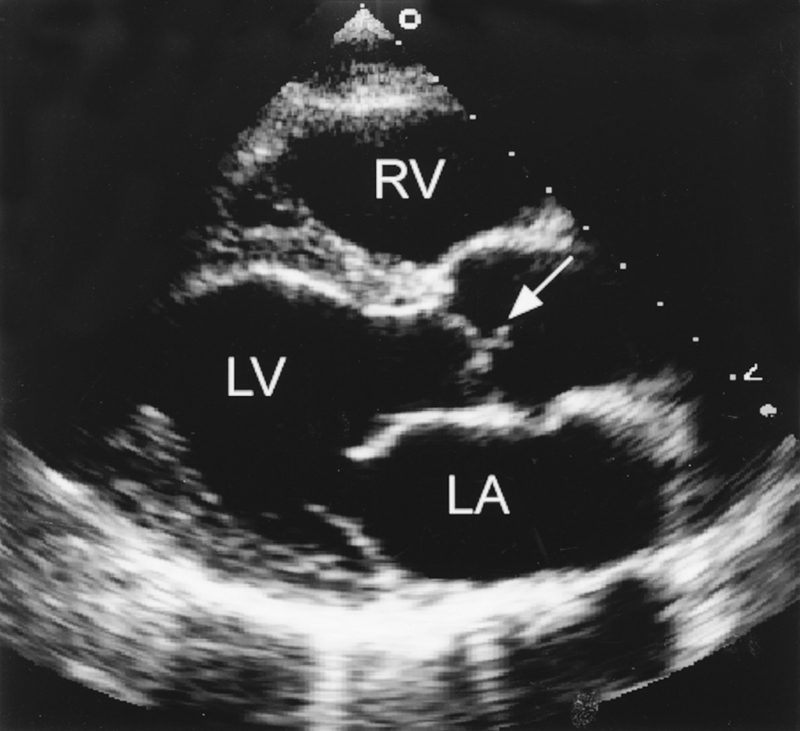

فحوصات تشخيصية لبعض امراض القلب والشرايين التاجية